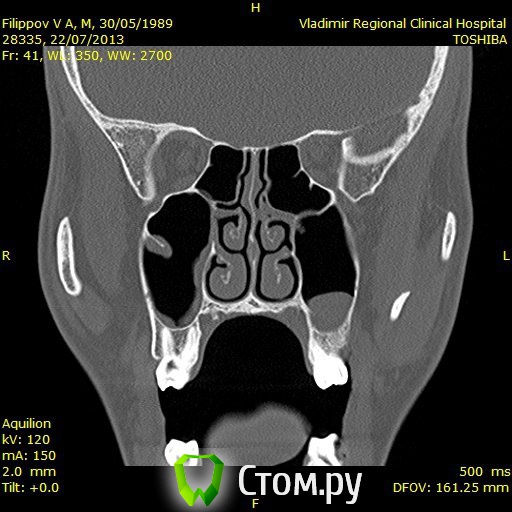

Доброго времени суток,помогите пожалуйстабеспокоит заложенность носа уже 3ий год,обший ослабленный иммунитет что выражается в частых простудах,возраст 25 лет,причина этого гдето в зубах,так как кроме этого проблем небыло никогда,когда начились эти проблему начал ходить к стомалогам мне сделали порядка 7 пломб,в одном был пульпит,как пульпит переличили стало легче но не до конца ,затем на мскт увидели кисту под депульпированной 7кой,

вот зуб пролечил у ильи мера,в 2 этапа,первый раз он сделал,и залили лекарство и сказал зуб врядли сохраним,через месяц второй прием все доделал и сказал что все хорошо,после этого общее состояние стало хуже,возможно из-за того что врач сказал что все с пульпы сливалось прямо в пазуху, вот это делали в марте ,после этого сделал мскт киста с зуба увеличилась с 1см до 1,5см, я лег в больничку местную и мнее ее вырезали,после этого прошел 1 месяц улучшений нет все также заложенность в носе и пониженный иммунитет,не подскажите что делать?кисту просто вырезали резекцую корня зуба не делали вот снимки до вырезания кисты после первого раза лечения каналов